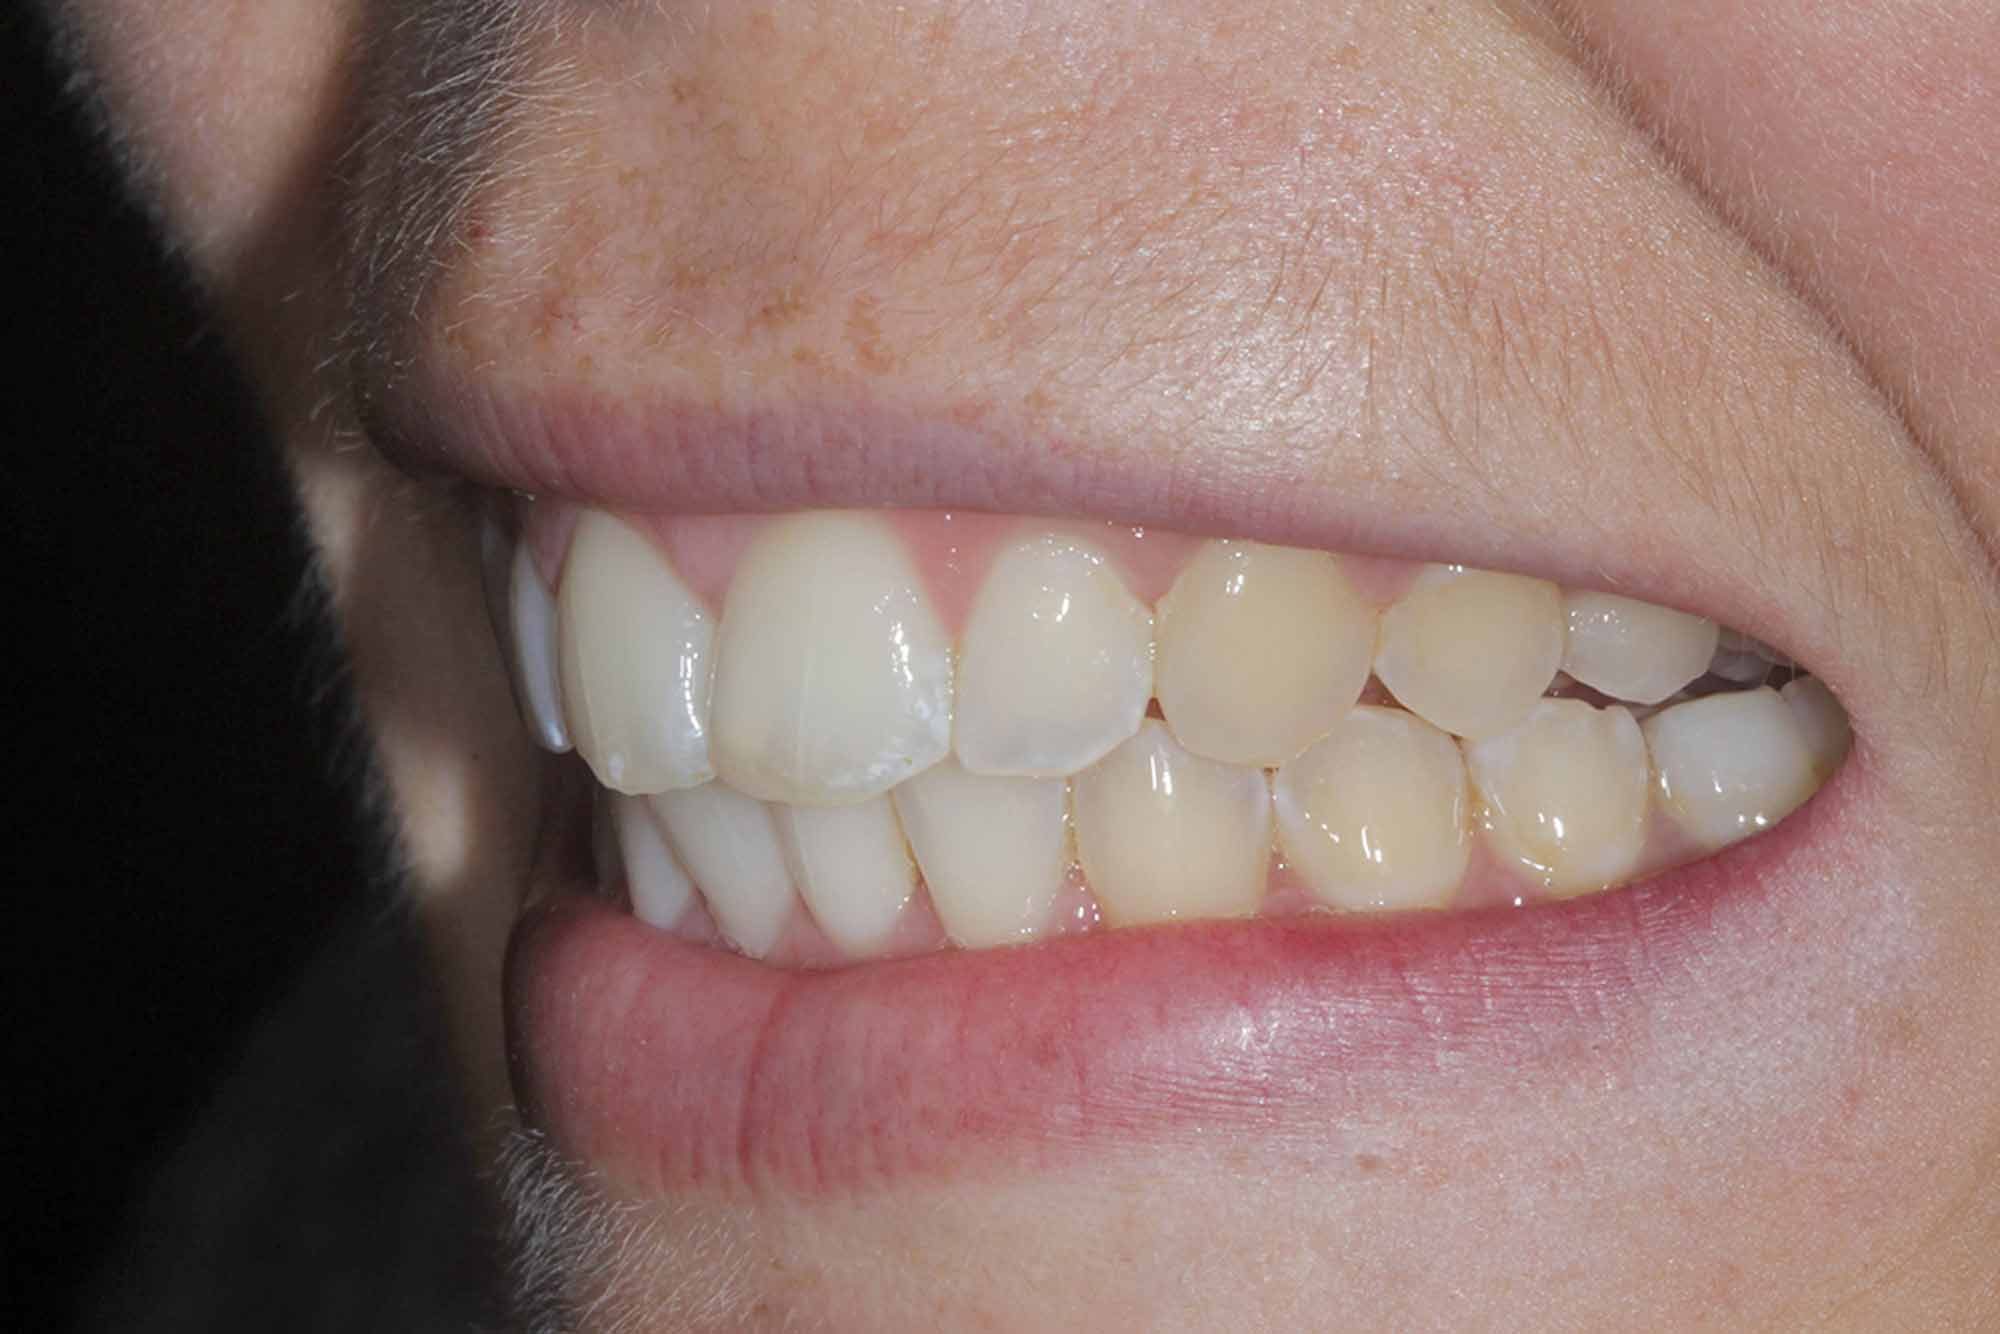

Outcome

The final result was another delighted patient and another beautiful smile completed following all the smile design protocols. This can incorporate any system needed as long as your planning process is sound and predictable each time.

Once the tooth positioning and colour were both at an exemplary stage, it was time to frame the result with composite direct edge bonding. This has been made much easier due to all the other factors. Our restorative material of choice for this case was Venus Pearl shade BL. This matched the patient’s newly whitened teeth perfectly.

The other factors had been carried out to such a high level, that the bonding stage was very straightforward and fairly easy to conduct. Using the right tools to blend the margins in and polish them to give this case even more longevity in the long run. The key to these cases is anatomy. Match the anatomy and proportions, and it will blend beautifully.